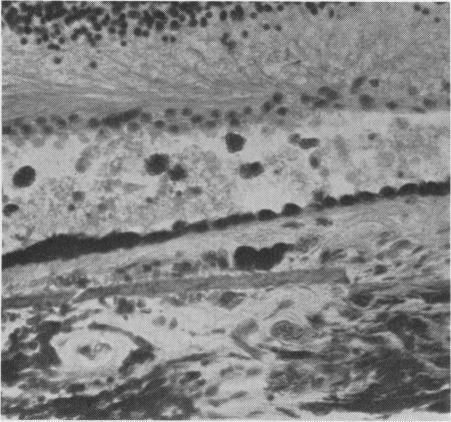

Fundus dystrophy with unusual features; a histological study.

Br J Ophthalmol. 1951 Dec;35(12):751-64. doi: 10.1136/bjo.35.12.751.